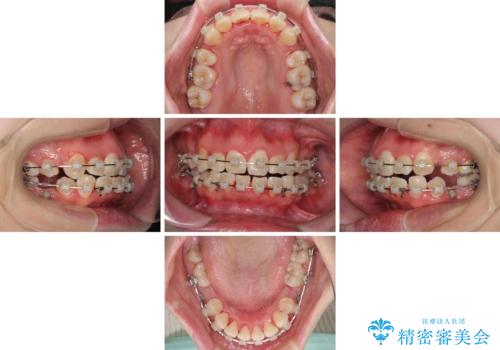

治療中に舌の突出癖が改善されず、下顎前歯が著しく前方に突出して反対咬合となってしまう局面がありました。

アンカースクリューを使用しながら舌癖の改善を図り、何とか咬み合わせを改善することができました。